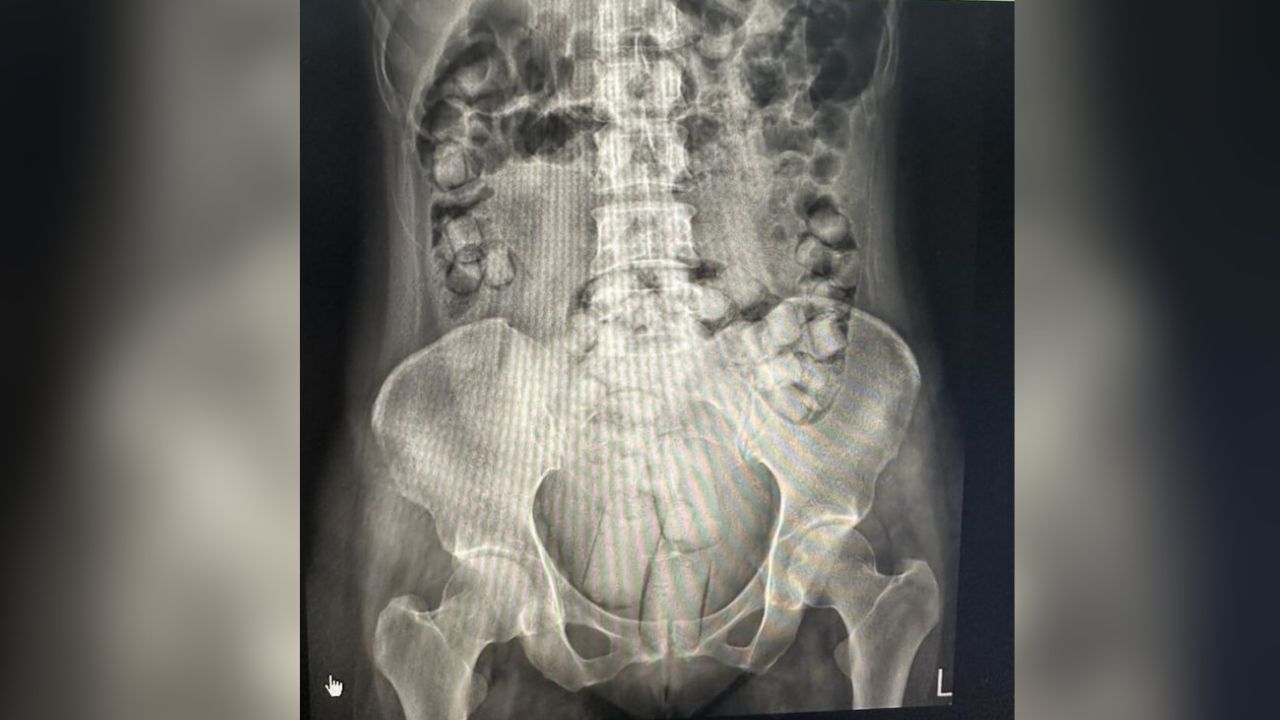

Officials said the pair were searched after they were seen behaving suspiciously, and a large quantity of heroin was found hidden in their bodies. Police said one woman concealed one package in her genital area and swallowed 60 packages, while the other concealed four packages in her genital area and swallowed a further 50 packages.